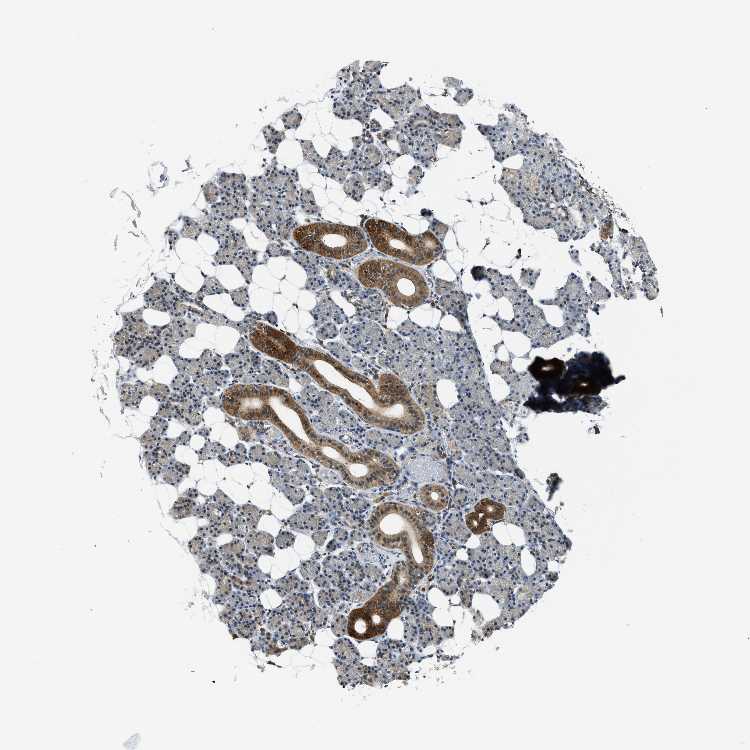

Antibody HPA019204

Glandular cells Low